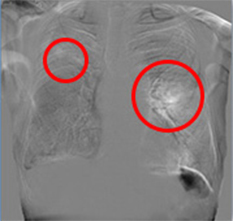

注意:赤枠は実際には表示されません。

◆変化が可視化され、新規病変の認識がしやすくなる。

◆肺門部や心臓裏の見落としやすい部位の病変が見つけやすくなる。

経時変化の差がドーナツ形状として現れることで、一見「変化なし」としがちな病変の大きさ変化が認識可能です。

肺門部裏は見落としやすく重要な読影ポイントですが、経時差分画像により一目で変化が確認出来ます。